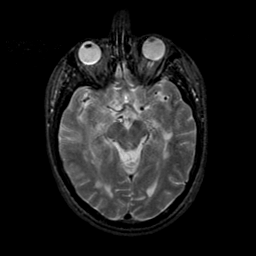

MR Study #9, April 14, 1991 -- Slice #21

[Home][Help][Clinical][Tour 1][Tour 2] Slice 21